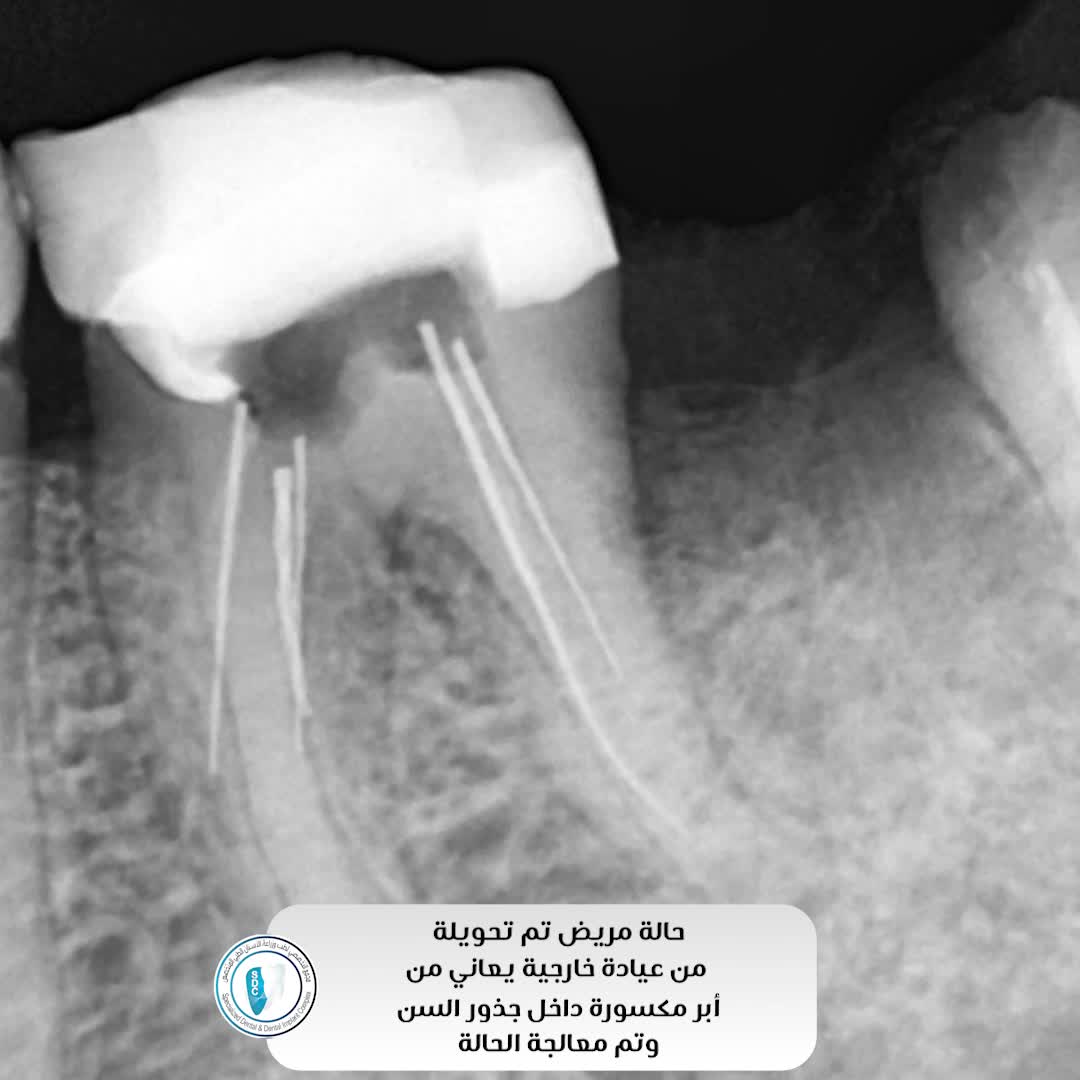

يتم علاج عصب الأسنان عادة من خلال إجراء يطلق عليه اسم جراحة الجذر، أو علاج العصب. خلال هذا الإجراء، يقوم الطبيب بإزالة العصب المتضرر من السن. هذا يتيح له فرصة تنظيف السن ومنع تشكل الأنسجة الجرثومية. بمجرد الانتهاء من هذا، يمكن للطبيب أن يملأ الجذر وتغطية السن، وإعادة الشكل له.